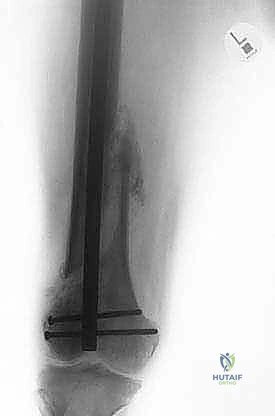

The modular prosthetic design is key to this reconstruction. It typically comprises:

* A proximal bipolar cup: This articulates with the native acetabulum.

* A modular body length: Chosen based on patient anatomy and the desired stump length. This segment often has a porous coating to encourage soft tissue ingrowth.

* A distal rounded, bullet-shaped tip: Designed specifically to prevent tissue penetration and features multiple fixation holes for reattaching the distal muscle ends.

Figure 2: A modular stump prosthesis illustrating its key components: a proximal bipolar head, porous coating for soft tissue ingrowth, and distal holes for muscle reattachment. Note the rounded distal tip to prevent tissue penetration.

We'll have a custom bullet-tip prosthetic extension ordered based on our templating from the preoperative imaging. The goal is to achieve a stump length that allows for effective prosthetic fitting and leverage.